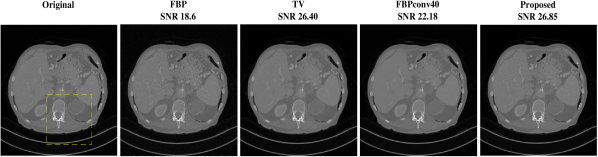

Fig. 2 (a) illustrates the reconstructions of a test image for case when measurement is noiseless. FBP is dominated by line artifacts, while TV satisfactorily removes these but blurs the fine structures. FBPConv and RPGD, on the other hand, are able to reconstruct these details. The zoomed version shows that RPGD is able to reconstruct the fine details better than the others. This observation remains the same when the measurement quality degrades. Fig. 2 (b) shows the reconstructions for 45-dB and 40-dB noise levels. In these scenarios, RPGD40 is significantly better than both FBPconv40 and TV.

Fig. 3 compares the reconstructions for the case when the noise levels are 45 dB and 35 dB. It is visible that FBPconv40 results in a noisy image and TV is again blurred. RPGD40 retains the fine structures and is the best performer.